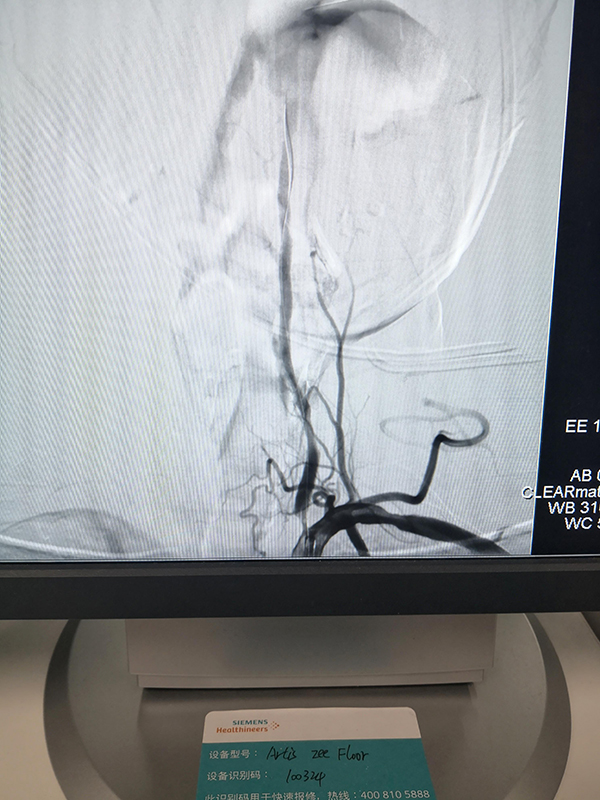

術前影像

因為及時溶栓,所以患者在轉診的路上意識便有所恢復,溶栓有效;到達柳州市人民醫院后,患者通過綠色通道直達介入室,根據患者病情進行急診取栓及支架植入手術,患者術后立即恢復清醒,四肢活動能力及語言能力恢復正常。